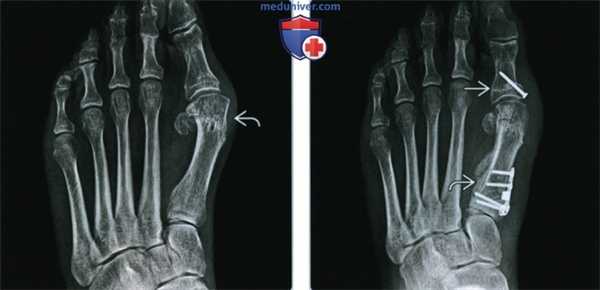

(Слева) Рентгенография в ПЗ проекции: пластика по Silver. Эта простая бурсэктомия (резекция медиального выступа головки первой плюсневой кости) не повлияла на деформирующую силу на первом пальце. У пациента варусное отклонение первой кости плюсны (>10° между первой и второй плюсневыми костями) и рецидивирующий hallux valgus.

(Справа) Рентгенография в ПЗ проекции, тот же пациент после остеотомии первой проксимальной фаланги и первой кости плюсны: теперь определяется ятрогенное укорочение первого пальца, что может привести к механической метатарзалгии.

(Справа) Рентгенография в ПЗ проекции, тот же пациент после остеотомии первой проксимальной фаланги и первой кости плюсны: теперь определяется ятрогенное укорочение первого пальца, что может привести к механической метатарзалгии. (Слева) Рентгенография в ПЗ проекции: бурсэктомия и шевронная остеотомия с боковым смещением головки первой плюсневой кости через участок остеотомии. Шевронная остеотомия нечетко визуализируется при ПЗ рентгенографии, так как имеет V-образную форму в сагиттальном сечении.